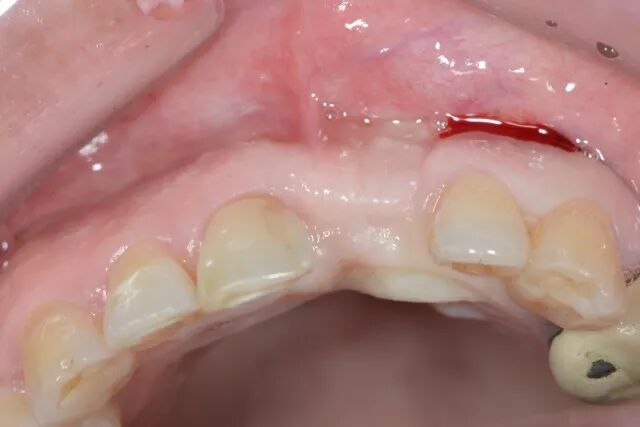

5.0線縫合 唇側(cè)

?

鄂側(cè)

術(shù)后四周? 顎側(cè)

唇側(cè)